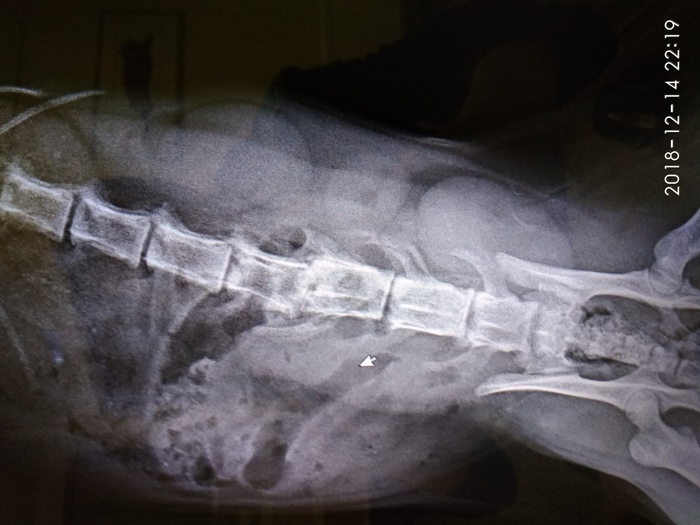

Этого кота зовут Сеня. Мы с друзьями его подобрали на трассе, в Санкт-Петербурге, когда все машины просто объезжали его в последний момент..Сеню кто-то сбил на большой скорости и теперь у него парализована вся нижняя половина туловища, включая задние лапки и хвост.

У Сени перелом позвоночника со смещением, кроме этого, он не может мочиться сам. Ветврач подарила нам катетер, с помощью которого нужно откачивать жидкость из мочевого пузыря примерно раз в сутки.Через каждые 48 часов, мы ставим ему уколы амоксициллина, назначенные ветеринаром, чтобы расслабить мышцы живота и, возможно, он сможет ходить в туалет сам, без помощи катетера.

Операция на позвоночнике возможна, но шанс, что она поможет, очень мал...Время идет на минуты.